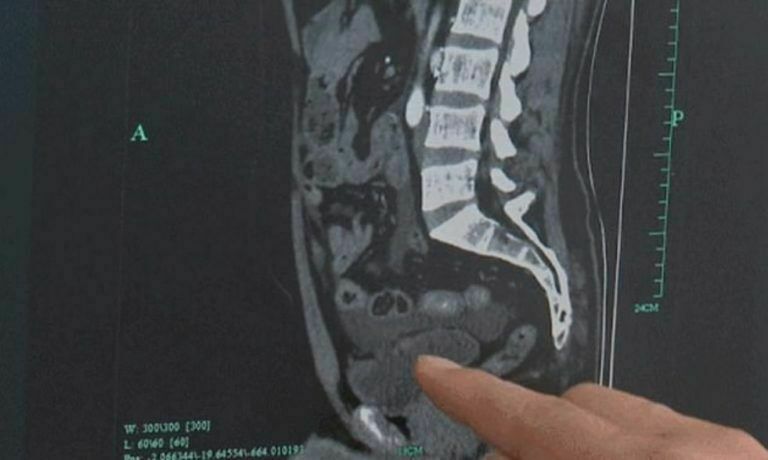

जसका कारण हूको मूत्राशय तीन भागमा फुटेको हो । यो घटना देखेर चिकित्सकहरू नै चकित भएका छन् ।

उनको सीटी स्क्यानको रिपोर्टमा मूत्राशयमा तीन प्वालहरू भएको देखिएको डाक्टरहरुले बताएका छन् । एउटा प्वाल उनको पेटसम्म पुगेको हुँदा आन्द्राको केही भाग मूत्राशयभित्र पस्न गएको पनि बताइएको डेलिमेलले समाचारमा लेखेको छ ।